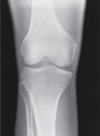

Describe the brightness of this image

Insufficient brightness